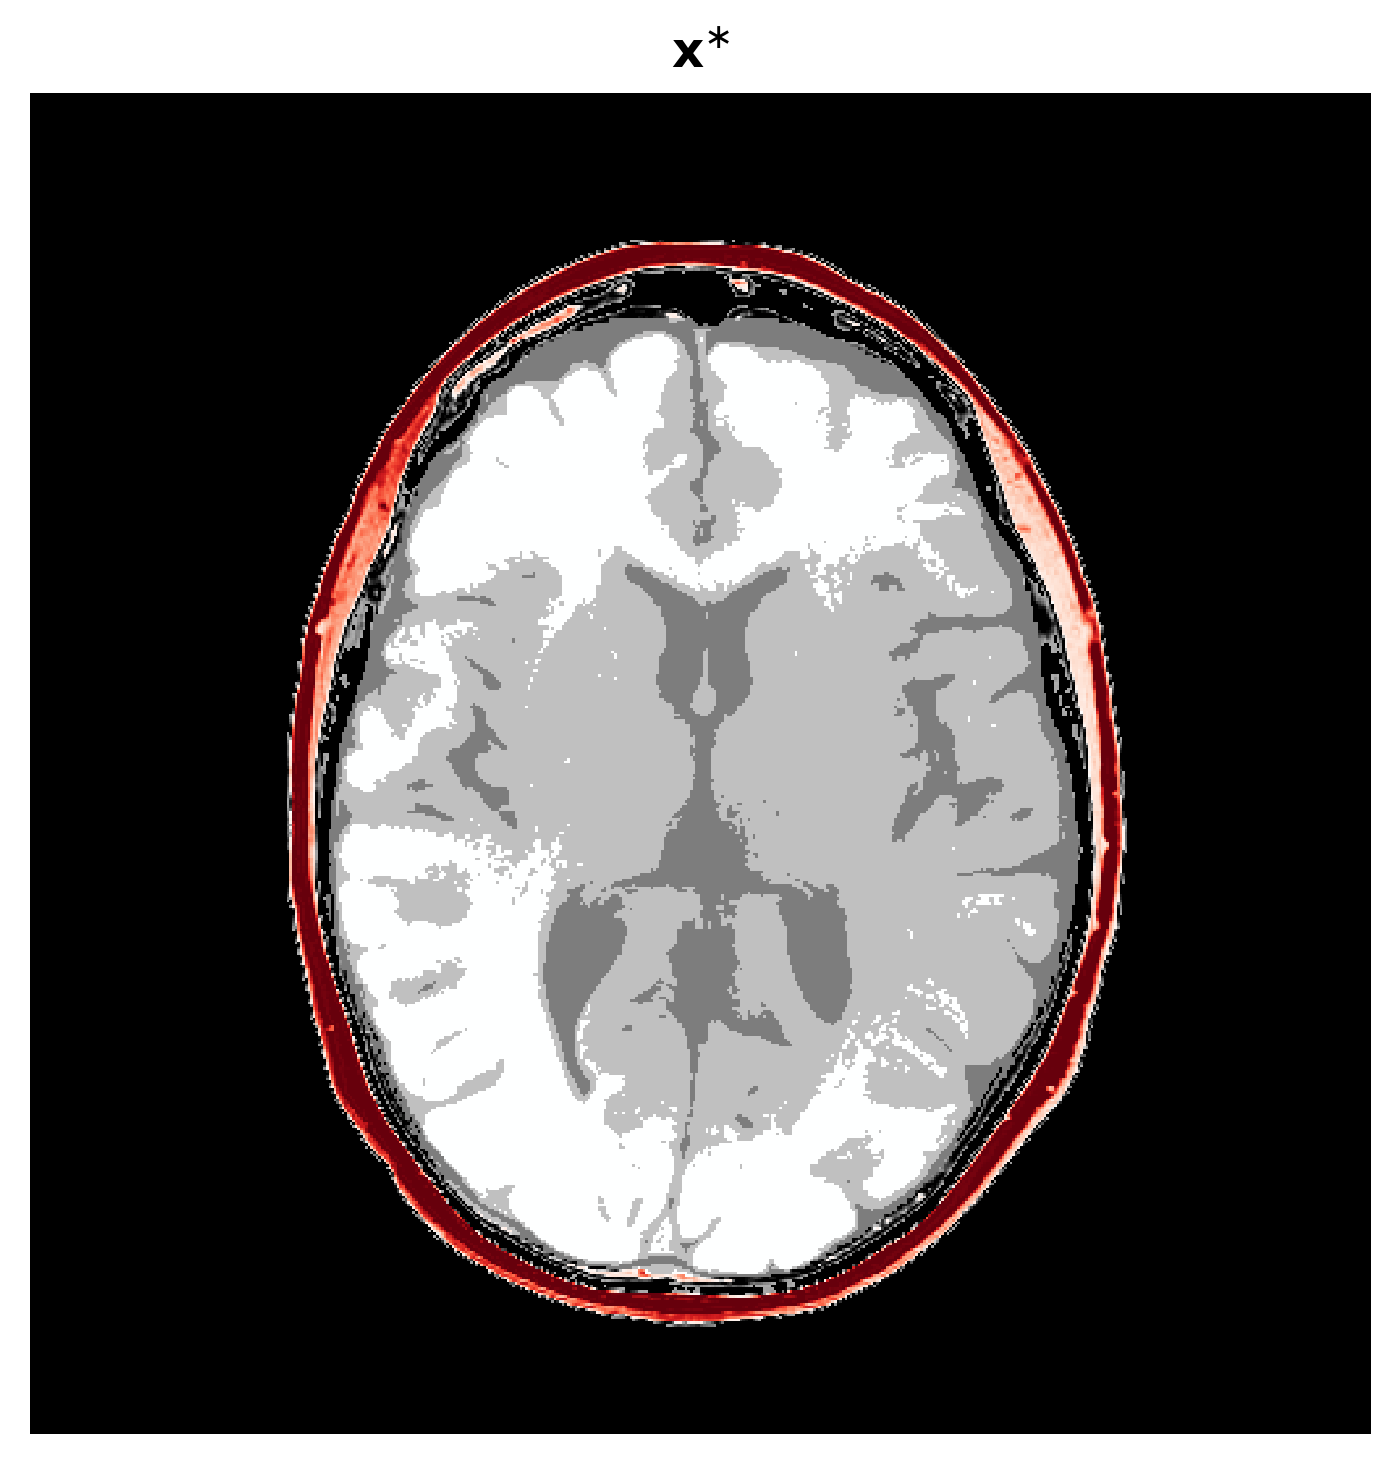

where is a starting point at which the gradient is calculated. Note, \equationrefeq:summ-data involves evaluating the forward physical model and its Jacobian adjoint . Thus this summary is informed by the physics (domain knowledge). As a result, the summarized data lives in the reduced image space (reduction factor of about ). According to Fluri et al. (2021), the informativeness of this summary statistic also implies that thus we propose to use the same conditional distribution learning objective as \equationrefeq:train-cond but replace the data with the summary . See Algorithm 1 in the Appendix for our full training process. The technical assumptions for the informativeness of this summary statistic are discussed in Appendix 4.5 alongside studies to understand the effect of deviations from the assumptions. One of the assumptions is that the starting point needs to be carefully chosen as it will affect how informative the summary statistic will be. For our application, is the acoustically correct model of the skull bone and a constant acoustic model inside the skull since the soft tissues inside the skull are the clinically relevant structures we care to image. Inclusion of the skull is needed so that the physical operators create meaningful results that inform the posterior. In practice, acoustic values of skull bone can be calculated from CT scans Aubry et al. (2003). See Figure 2 for an example of and Figure 2 for the physics-informed summary it creates.

\subfigure

|